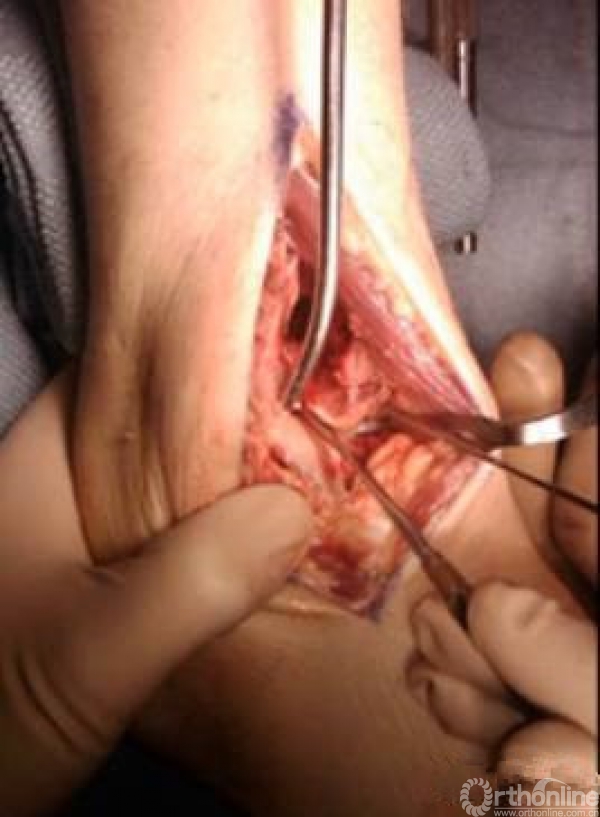

术中技巧

1.粉碎的骨折 采取小块靠大块

对于这样的骨折,充分显露之后,先从后面开始,逐步把小块往大块上复位,逐渐复位到最前面。

2.中心粉碎骨折

充分牵引,撑开,将关节面的骨折块先找到摆放在合适的位置

用克氏针将关节面的骨块应用排筏技术先固定好,从下方观察关节面的复位情况,并且确认骨块不会向上推起

植骨

然后将骨块前后和左右进行压实后进行固定